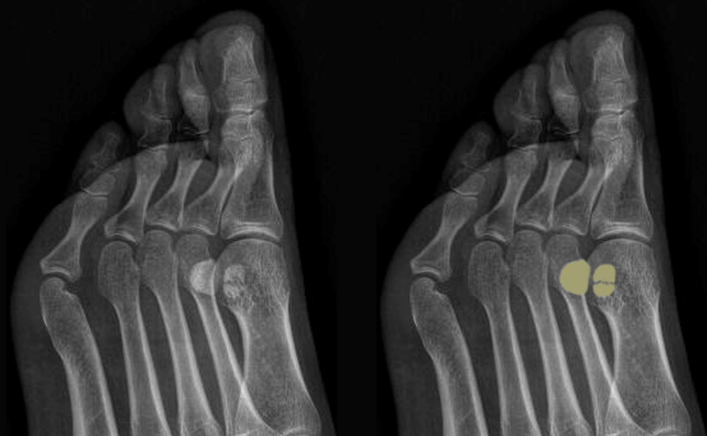

图6:拇趾籽骨

图7:籽骨骨折